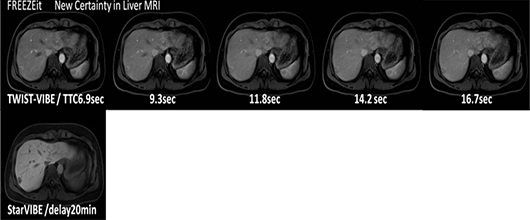

進化した体動補整技術と息止め不要の3D腹部撮像が可能な「FREEZEit」

腹部系の3D撮像では、高い空間分解能を維持したまま、体動によるアーチファクトを大幅に軽減し、息止め不要の3D腹部撮像が可能になりました。ラジアルサンプリングの採用で通常呼吸下での造影3D撮像を可能にする“syngo StarVIBE”を搭載しています。

◆進化した腹部系の造影3D撮像と体動補正を利用した撮像例

[肝臓造影撮像例]